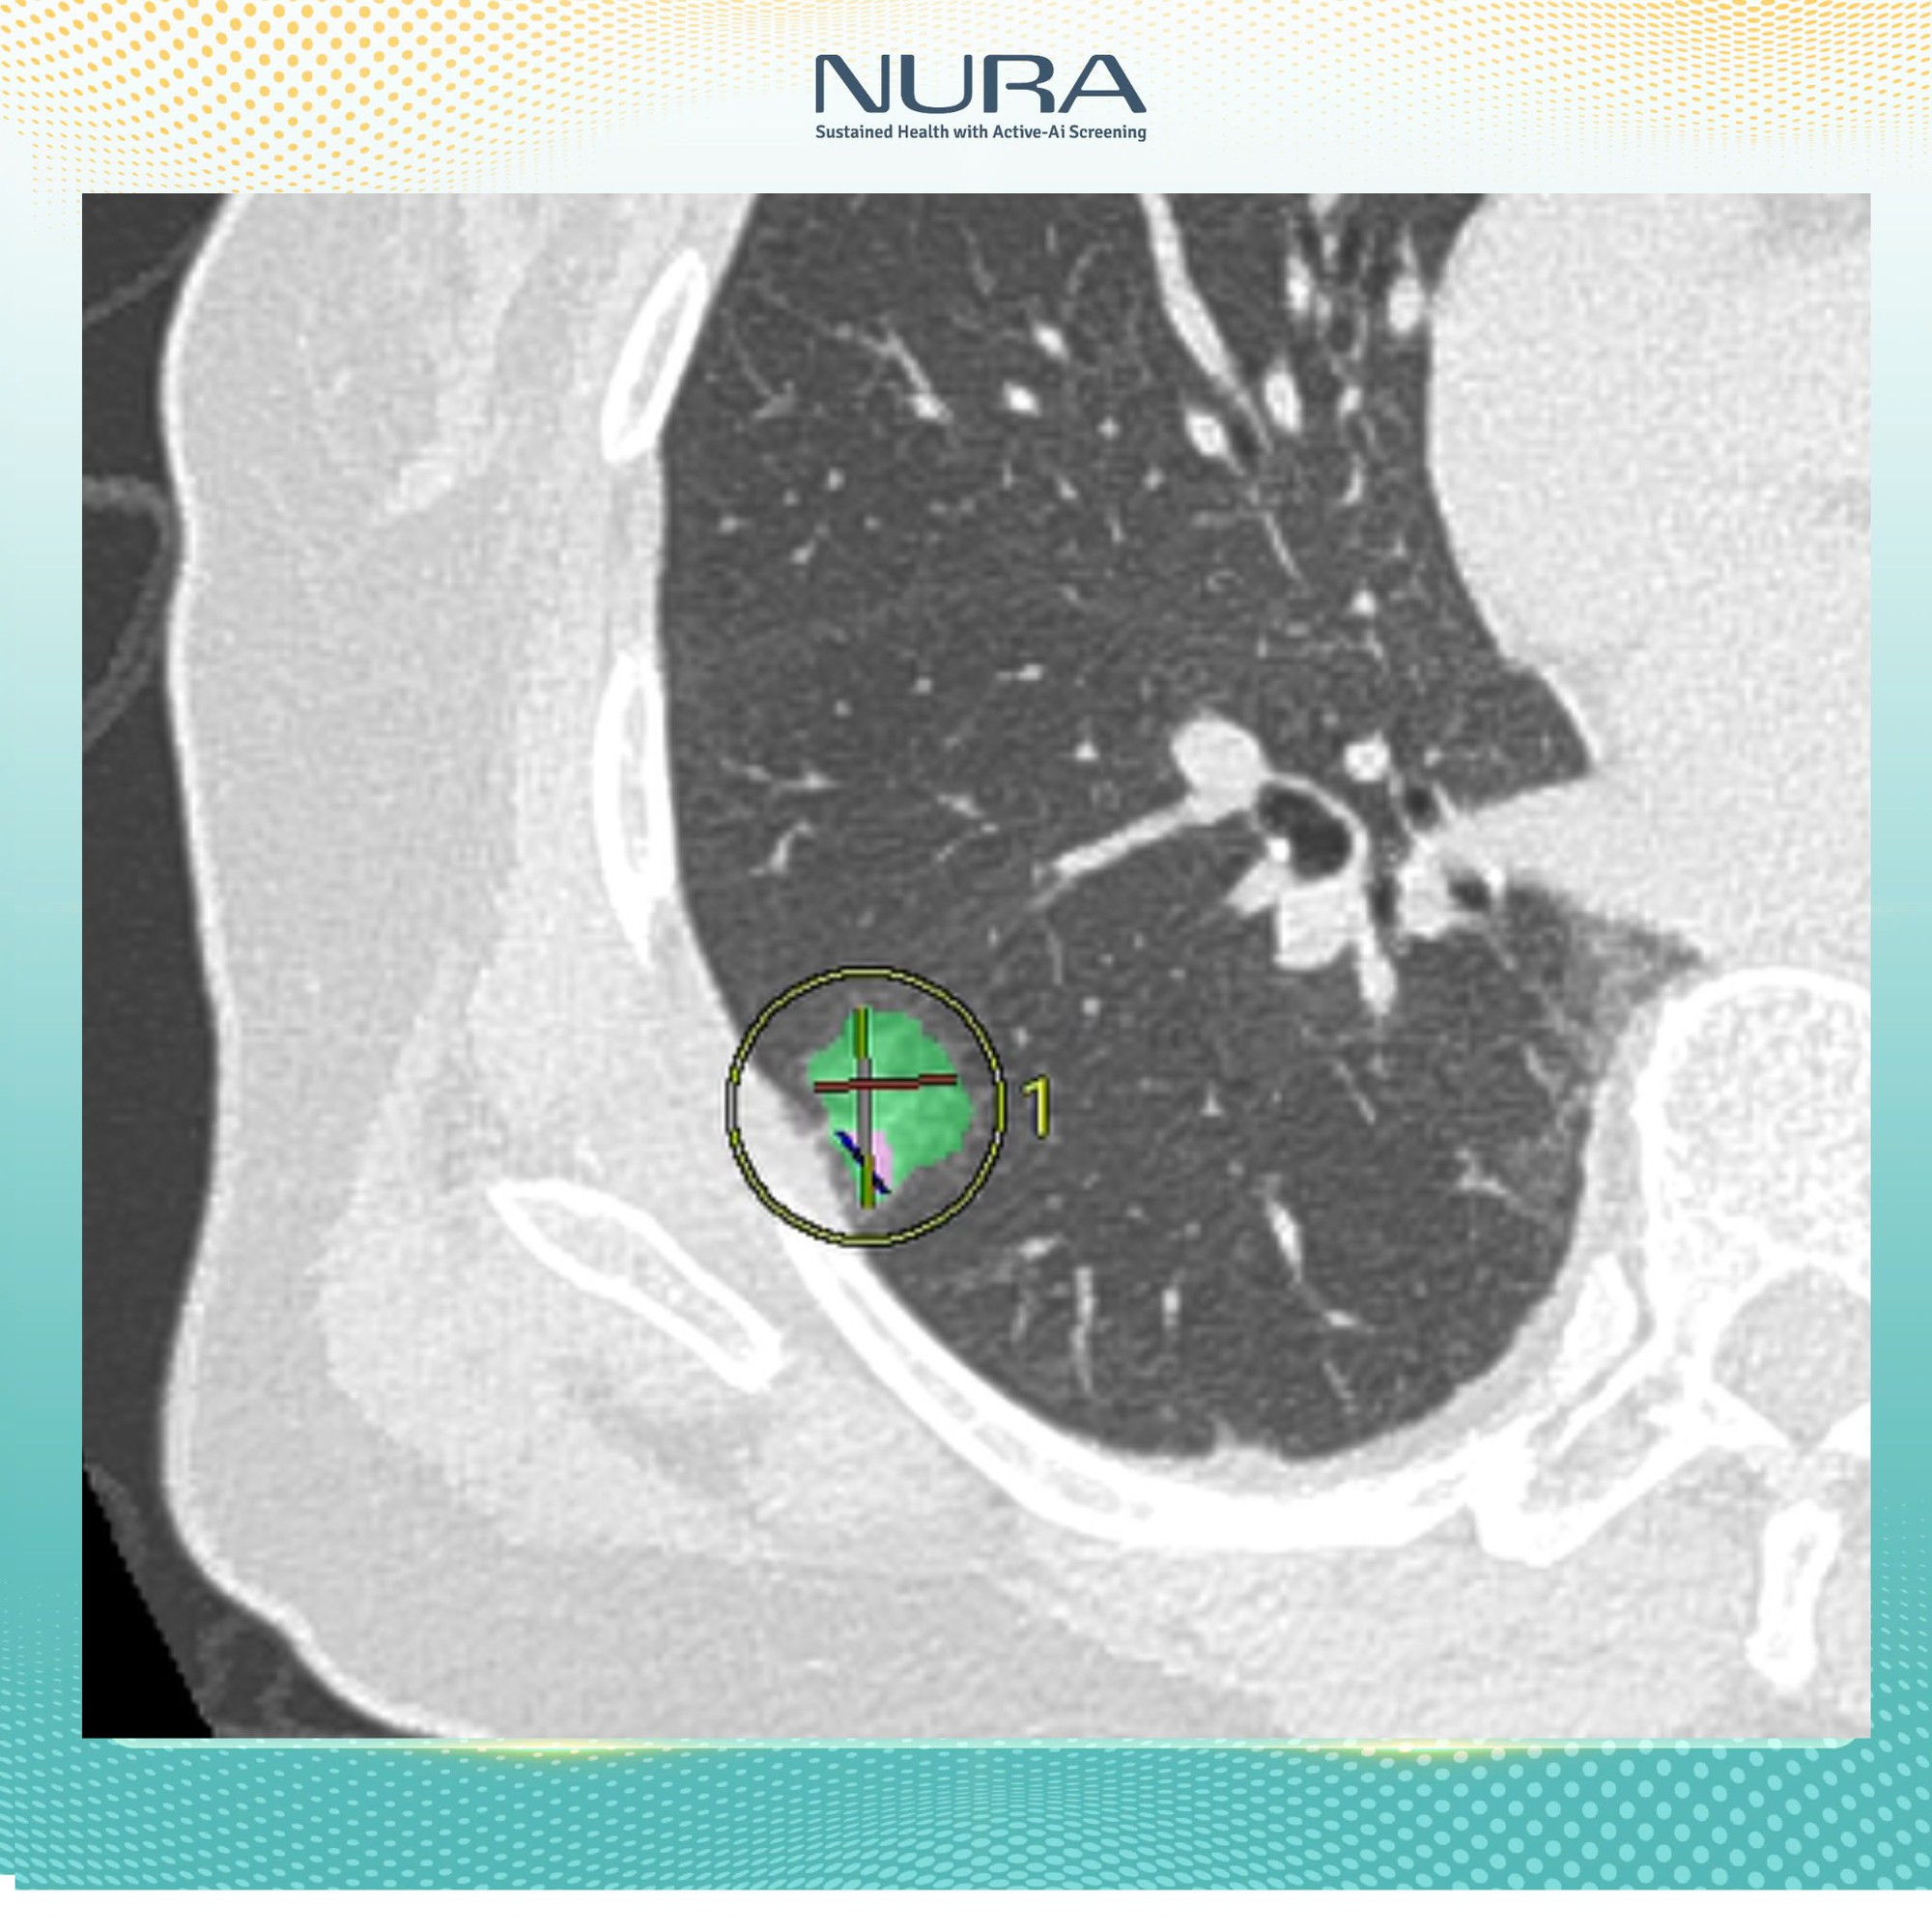

Trong số các thiết bị nổi bật tại trung tâm, máy chụp CT tại đây đã được các bác sĩ Nhật Bản công nhận là “chìa khóa vàng” trong tầm soát phát hiện ung thư. Được vận hành bởi đội ngũ bác sĩ giàu kinh nghiệm và tích hợp AI, hệ thống máy chụp này không chỉ giúp phát hiện các tổn thương rất nhỏ mà còn đảm bảo an toàn tối đa cho người được thăm khám.

“Công nghệ AI của NURA không chỉ đơn thuần là công cụ hỗ trợ, mà còn đóng vai trò quan trọng trong quy trình phân tích và nhận diện hình ảnh. Bằng cách thu thập và xử lý dữ liệu hình ảnh y khoa từ hơn 400 triệu ca bệnh được Fujifilm Nhật Bản lưu trữ trong suốt 10 năm, AI có thể nhận diện sớm các tổn thương bất thường – từ những nốt nhỏ nhất, kích thước từ 1mm trở lên.

Tại NURA, công nghệ AI được xây từ 400 triệu bộ dữ liệu hình ảnh và tích hợp trong hệ thống tầm soát công nghệ cao, cho phép lưu trữ và phân tích dữ liệu hình ảnh rõ nét, vượt trội so với phương pháp chụp cắt lớp truyền thống”, Đại diện NURA chia sẻ với báo chí.

- Lần thứ hai là chụp lồng ngực và ổ bụng, hỗ trợ phát hiện các tổn thương dù là từ 1mm tại phổi, gan, tụy, thận và các cơ quan quan trọng khác.

Chỉ sau vài phút, kết quả sẽ được gửi về dưới dạng các hình ảnh cắt lớp chi tiết. Những lát cắt này cho phép bác sĩ phát hiện các tổn thương có kích thước từ 1mm, giúp việc chẩn đoán trở nên chính xác và nhanh chóng hơn rất nhiều.

- Về tính chính xác: AI không chỉ giúp phát hiện tổn thương từ rất sớm, mà còn tự động đo kích thước từng nốt nghi ngờ, đếm số lượng, đánh giá mức độ nguy cơ và hỗ trợ bác sĩ trong việc đưa ra quyết định chuyên sâu.